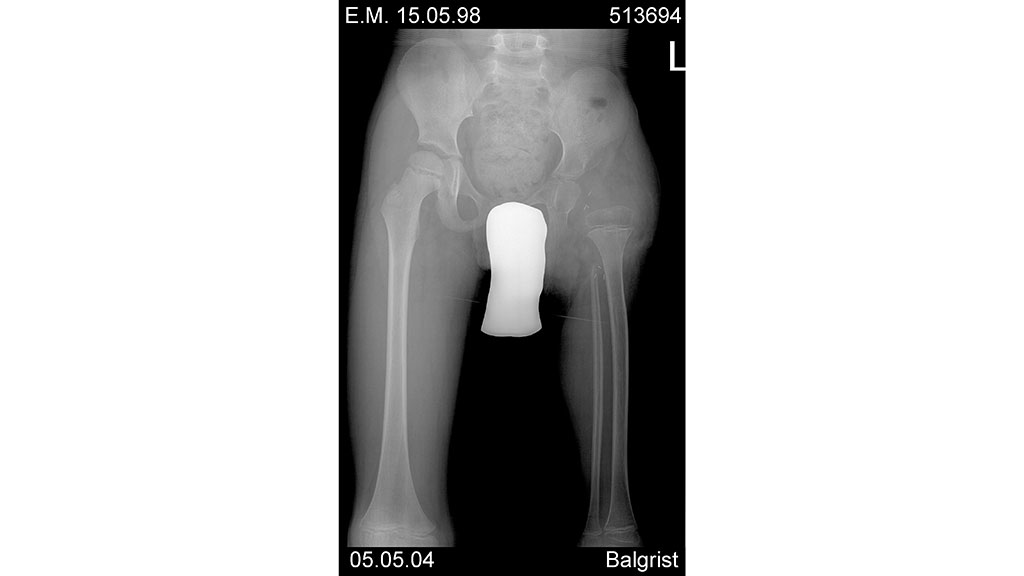

Hier handelte es sich um ein heute 16-jähriges Mädchen mit einer Dysmelie (Abb. 1) der linken unteren Extremität, deren Unterschenkel als langer, spitzer, nicht belastbarer Dorn gewachsen ist. Um einen belastungsfähigen Stumpf zu erhalten, wurde 2001 eine Knie-Exartikulation durchgeführt. Die gleichseitige Hüfte ist dysplastisch (Abb. 2) und luxiert nach ventral, hinzu kommen Stuhl- und Harninkontinenz. Nach der Knie-Exartikulation war der Stumpf nun belastungsfähig, aber nicht alleine tragfähig, da die Hüfte der Belastung nicht Stand hielt (Abb. 3).

Die Orthopädie-Techniker entschieden sich für eine Oberschenkelprothese mit einer querovalen Schaftform sowie einen Beckenkorb, um die luxierende Hüfte zu stabilisieren. Der Hüftgelenksdrehpunkt war nicht zu lokalisieren. Bei einer Flexionsbewegung der Hüfte rotierte der Trochanter Major nach ventral-cranial. So wurde beschlossen, im Hüftgelenksbereich eine doppelachsige Zahnsegmentschiene aus Titan zu verwenden, die eine bestimmte Eigenelastizität mit sich brachte. Diese Elastizität war nötig, um die erforderliche Bewegungsfreiheit in der Hüfte gewährleisten zu können, ohne dass die Patientin die Schiene in kürzester Zeit zerbrach. Hier verwendeten die Techniker ein vierachsiges Kniegelenk und einen TruPer Fuß (Abb. 4).